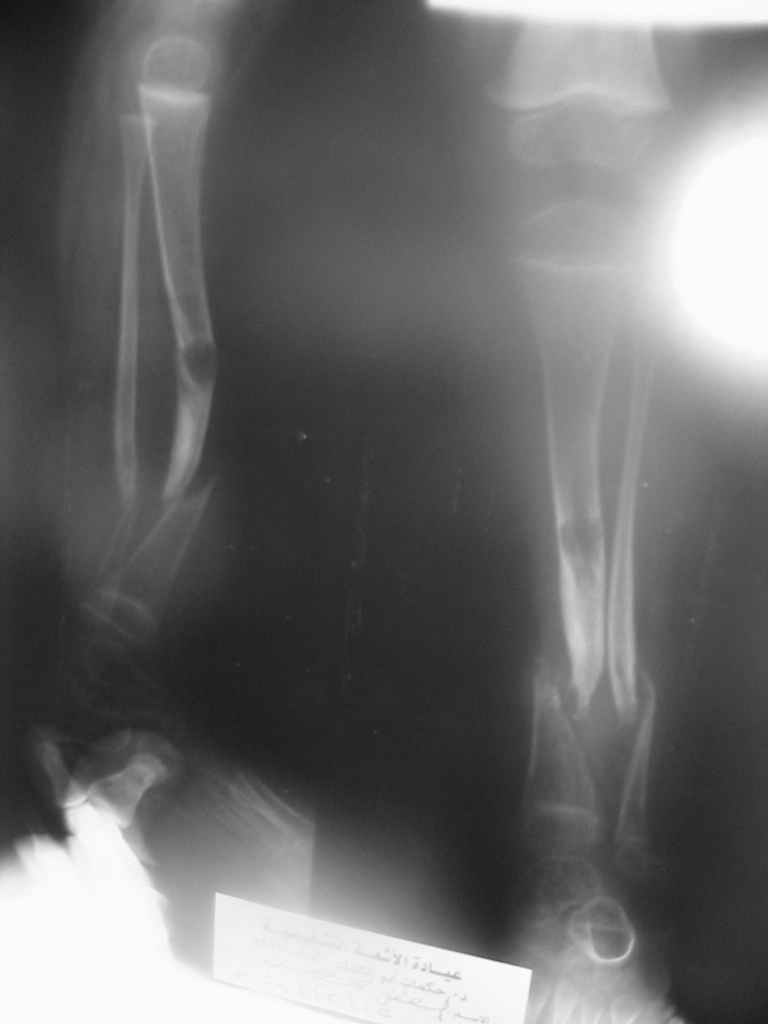

Neurofibromatosis

Uvazaemie Kollegy, Ko mne obratilsa malchik dva s polovenoi goda, stradaet ot vrozdennogo loznogo sustava N-3 kostei goleny,

Kakie budut soobrazenjia po planu ego lechenjia? Sposibo vsem za ranee Castro